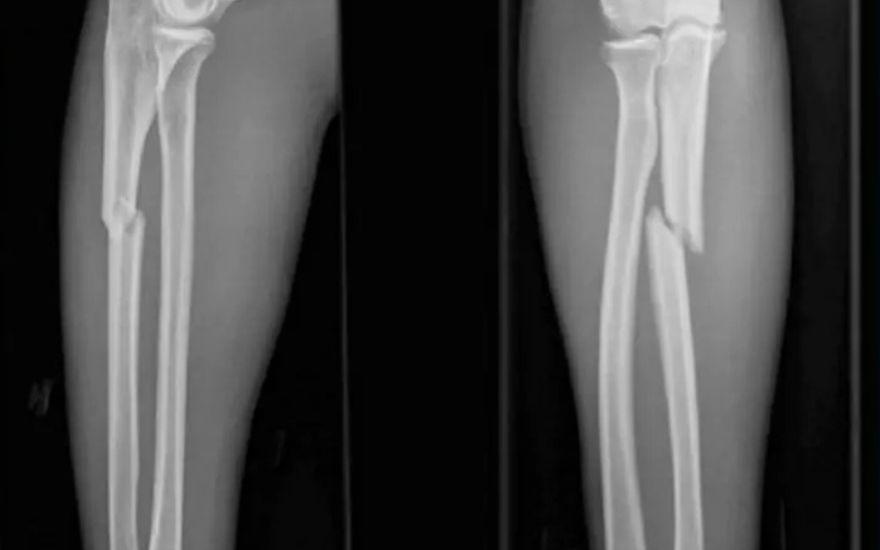

Nhận biết chậm liền xương qua phim chụp X-quang: Để thấy rõ nhất tình trạng lành xương đang diễn ra như thế nào? Hoặc nếu nghi ngờ đang gặp phải tình trạng chậm liền xương, người bệnh hãy yêu cầu bác sĩ cho chụp X-quang, những hình ảnh chụp sẽ cho thấy rõ tình trạng đang diễn ra.

Chụp X-quang cho thấy hình ảnh rõ nét quá trình chậm liền xương